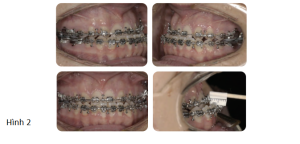

Phân tích case: Chỉnh nha tiền phẫu thuật cho bệnh nhân bị móm, hàm dưới đưa ra trước và lệch trái

Bệnh nhân có kiểu xương hạng III với thiểu sản xương hàm trên và xương hàm dưới đưa ra trước, lệch nhẹ sang bên trái. Bệnh nhân có tăng kích thước dọc, với độ lộ răng cửa tối thiểu ở tư thế nghỉ và lộ hoàn toàn khi cười. Đưa xương hàm trên ra trước sẽ giải quyết được tình trạng lõm mặt khi nhìn nghiêng và kết quả là tăng độ lộ răng cửa nhiều hơn, cho thấy có thể cần tác động vào phần trước xương hàm trên. Lực tác động vào phần sau xương hàm trên (lớn hơn lực tác động vào phần trước, nghĩa là đẩy không đồng nhất) được yêu cầu để giải quyết độ cắn trùm giảm và xu hướng cắn hở phía trước (móm). Lùi xương hàm dưới kết hợp xoay sang bên phải sẽ giải quyết được tình trạng xương hàm dưới đang nhô ra và bất cân xứng.

Qua thăm khám, bác sĩ chỉ định bệnh nhân cần chỉnh nha trước phẫu thuật hàm. Và các mục tiêu điều trị chỉnh nha bao gồm:

- Làm đều và làm phẳng các cung răng: Dàn đều răng bằng cách sử dụng dây cung đàn hồi ở thời điểm bắt đầu chỉnh nha tiền phẫu thuật. Làm phẳng cung răng thực hiện chủ yếu bằng dây cung SS (thép không gỉ).

- Phối hợp 2 cung răng: Đánh giá sự phối hợp 2 cung răng trong tương lai được thực hiện thông qua mẫu hàm nghiên cứu trước điều trị. Trong trường hợp này, phần nong rộng cần thiết ở cung răng trên có thể đạt được nhờ sử dụng dây cung bằng thép không gỉ hình chữ nhật.

- Làm mất bù trừ: Trong trường hợp này, cần làm mất bù trừ của cung hàm trên và hàm dưới để tạo ra độ cắn chìa âm phù hợp trước phẫu thuật và cho phép các dịch chuyển phẫu thuật mong muốn để hoàn toàn thúc đẩy sự thay đổi mong muốn trên gương mặt.

Việc làm mất bù trừ của cung hàm trên đòi hỏi phải dựng trục nhóm răng trước hàm trên. Điều này đạt được bằng cách nhổ các răng cửa bên hàm trên có kích thước nhỏ để tạo ra khoảng trống thích hợp. Ở cung hàm dưới, việc làm mất bù trừ đạt được bằng cách làm nghiêng ngoài các răng cửa hàm dưới.

- Duy trì đường giữa hàm dưới với đường giữa cằm: Trong trường hợp này, cung hàm dưới được điều trị không nhổ răng. Vì đường giữa hàm dưới trùng với cằm ở thời điểm bắt đầu chỉnh nha tiền phẫu thuật, nó được duy trì trong suốt giai đoạn làm phẳng và làm đều cung hàm dưới.